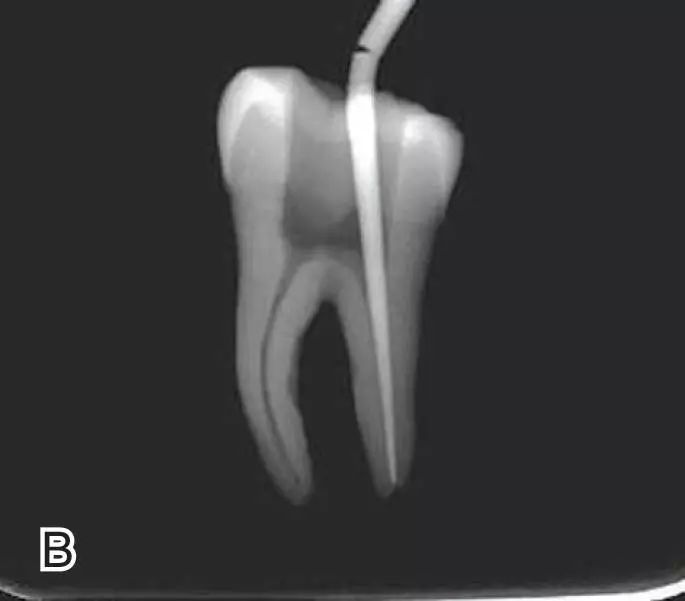

连续波加压

将携热器工作尖向根尖加热加压至距参照点约2 mm处,关闭加热器,保持根向压力,使工作尖前进到参照点处。保持加压状态10秒钟。

退出携热器工作尖

开启加热器1秒钟,迅速退出携热器工作尖,带出中上段多余牙胶尖。用小号垂直加压器向下加压,完成根尖段的充填。